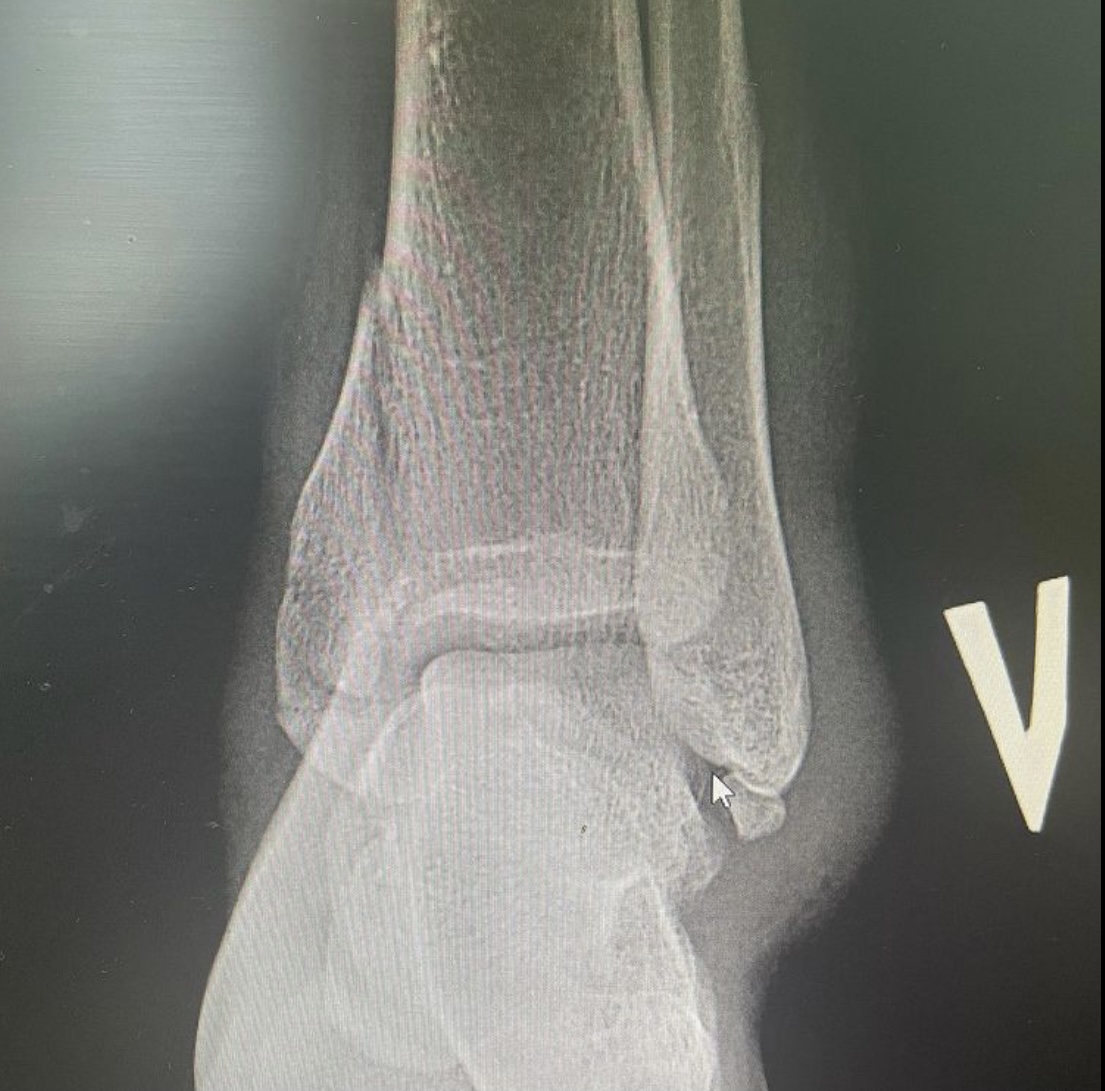

Врач – травматолог – ортопед 7-ой Городской клинической больницы Руслан Ильгизарович Закиров показывает рентген-снимки переломов, которые получили пациенты во время езды на самокате.

Во втором случае девушка 23 лет получила оскольчатый перелом дистального эпиметафиза большеберцовой кости. Также выполнен остеосинтез пластиновинтами и спицами. Данный случай осложнялся наличием внутрисуставного перелома с импрессией суставной поверхности.